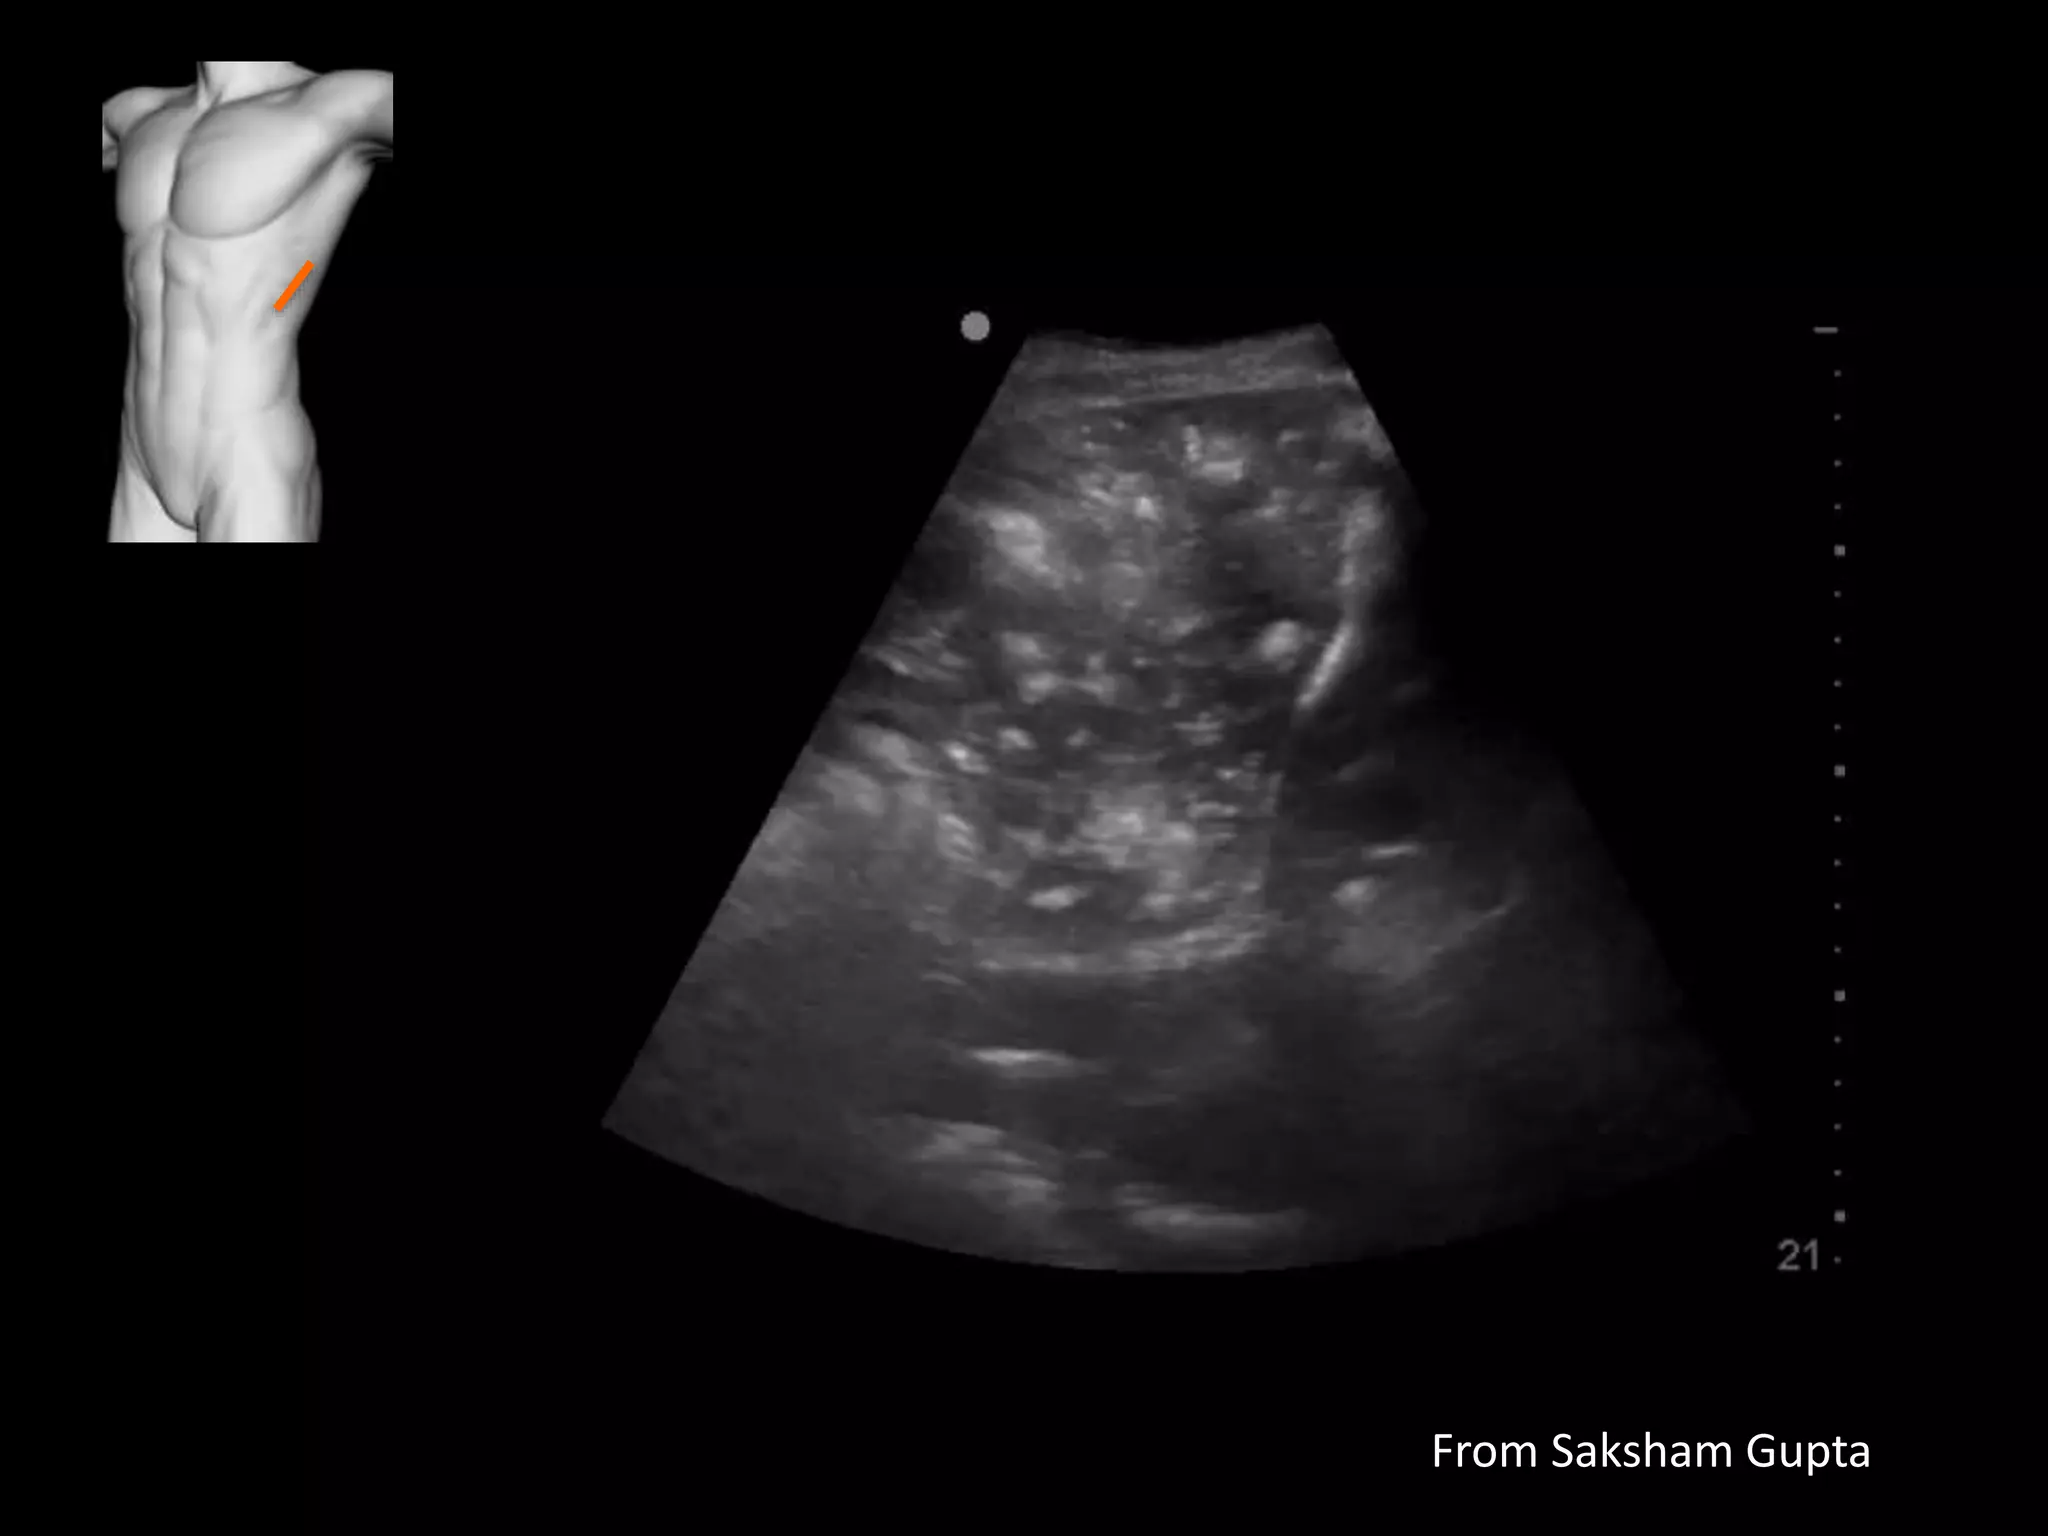

Case study 7

• Alcoholic, poor state of health

• Fever, weight loss

From Saksham Gupta

• Empyema